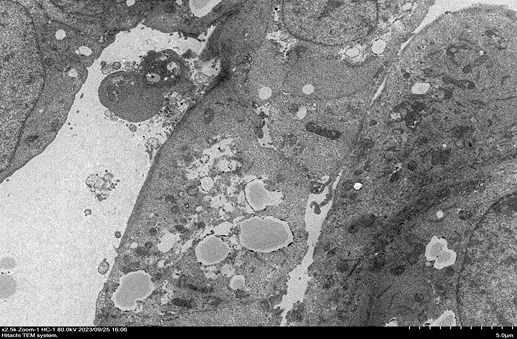

肝細胞超薄切片 X 2500